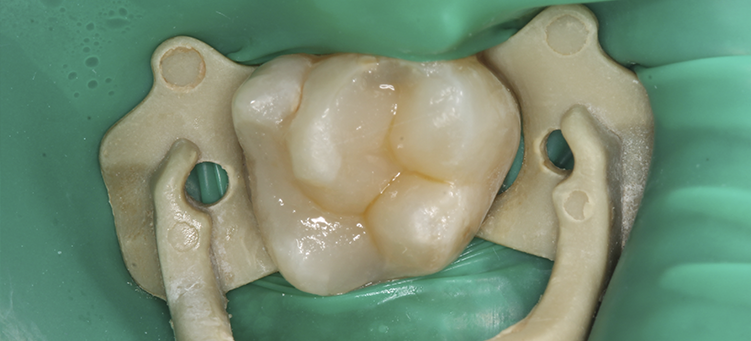

Эстетическая реставрация зубов

Лечение кариеса зубов